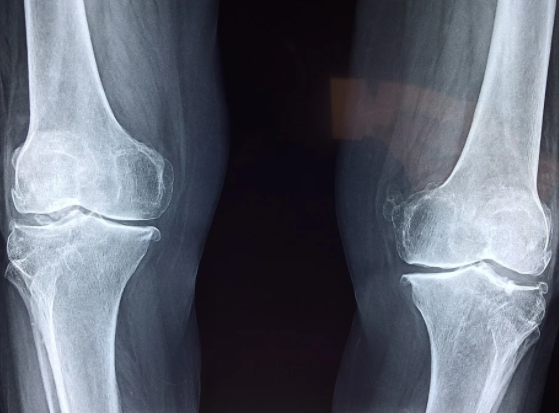

무릎 연골이라는 것은 한번 손상되기 시작하면 자연적으로 치유되지 않고, 계속 방치하게 되면 손상 부위가 점점 커지게 되어서 퇴행성 관절염을 앞당기게 되는 원인이 된다.

무릎 관절에 어떤 이유가 되었든 부담을 주게 되면 연골을 손상시켜서 무릎 관절염을 발생시키기도 한다.

무릎 연골 관절에는 허벅지뼈와 정강이뼈가 맞닿아있다고 한다. 이들의 뼈 끝에 있는 골연골은 뼈가 서로 부딪히면서 손상이 되지 않도록 하는 역할을 하게 되는데, 우리가 무릎에 무리를 줄 수 있는 행동이나 운동을 반복하게되면 뼈를 감싸고 있는 연골이 손상되기 때문에 평소에 무릎이 자주 아프다면 아래에서 언급하는 무릎 연골 손상 대표적 증상 TOP 6에 대해서 알아보고 자신이 해당하는지 파악해보기 바란다.